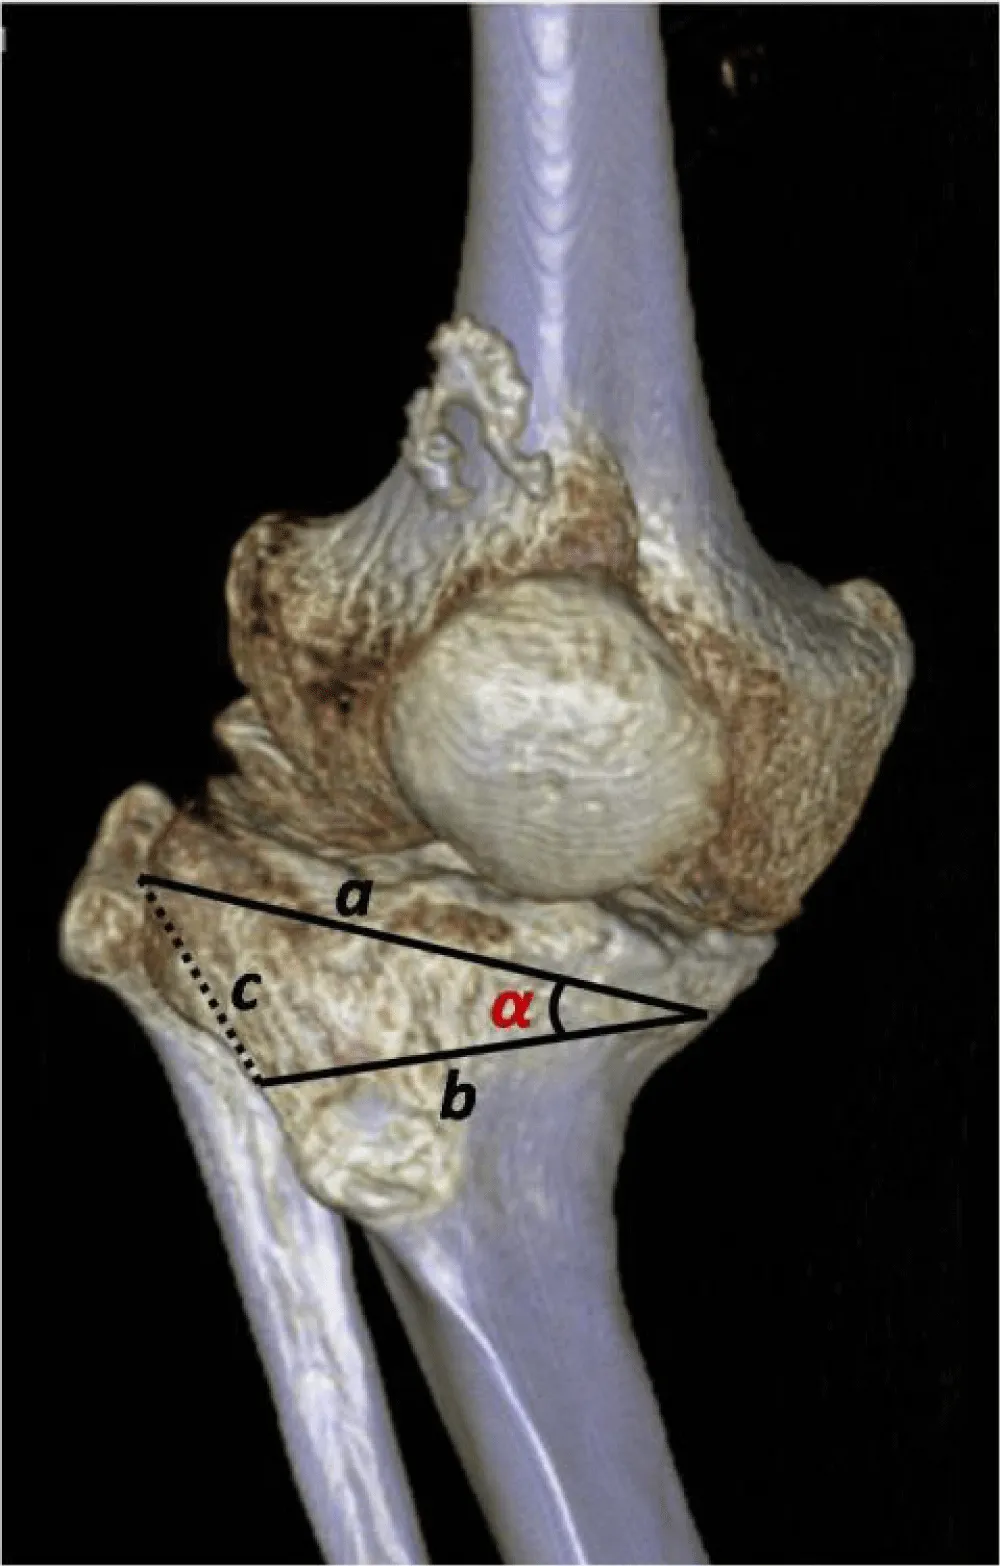

A) First step: Miniaci method (Figure 5).

Planning was performed using the Miniaci method on a weight-bearing radiograph of the entire lower extremity, as follows:

B) Second step: Trigonometric calculation.

Given the sides a and b (measured in the AP projection of the last preoperative X-ray) and the angle C between them (calculated using the Miniaci method), the cosine theorem (Figure 6) must be applied to calculate side c (Figure 7).

Calculations determined that the base of the tibial bone wedge to be resected should measure 3.1 cm. During an opening tibial osteotomy, specific instrumentation is utilized to achieve precise angular correction based on the Miniaci method. This eliminates the need for extra calculations that are necessary for a closing osteotomy.